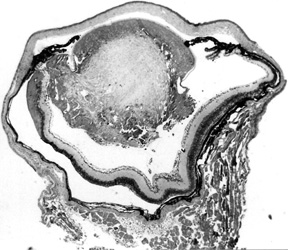

Figure 1b. Higher power view of lens in Fig. 1a.

The lens fibers are disorganized and some retain the nuclei.